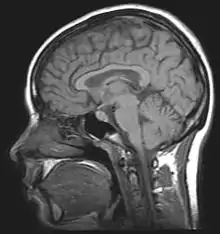

Alcohol-related brain damage[1] alters both the structure and function of the brain as a result of the direct neurotoxic effects of alcohol intoxication or acute alcohol withdrawal. Increased alcohol intake is associated with damage to brain regions including the frontal lobe,[2] limbic system, and cerebellum,[3] with widespread cerebral atrophy, or brain shrinkage caused by neuron degeneration. This damage can be seen on neuroimaging scans.[4]

Neuroimaging is used to study the effect that alcohol has on the brain. The two main imaging methods are hemodynamic and electromagnetic. These techniques have allowed for the study of the functional, biochemical, and anatomical changes of the brain due to prolonged alcohol abuse.[2] Neuroimaging provides valuable information in determining the risk an individual has for developing alcohol dependence and the efficacy of potential treatment.[2][17]